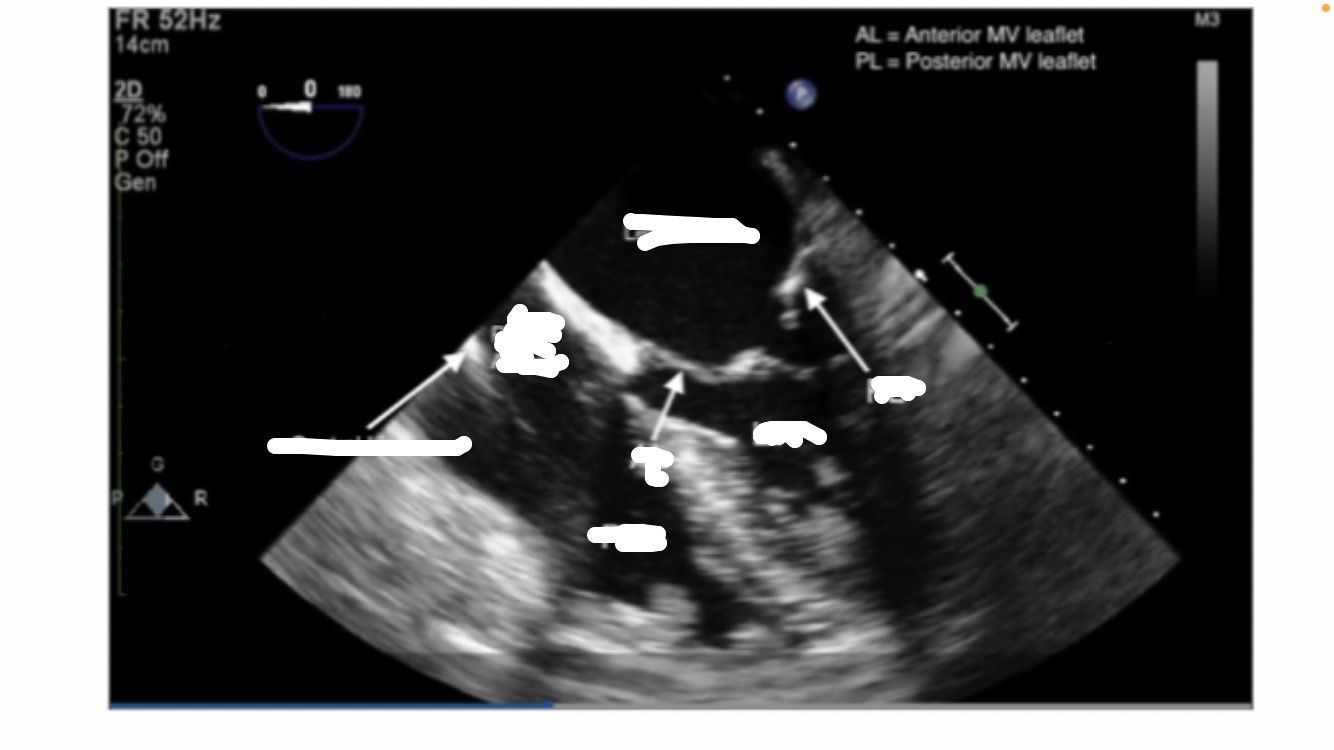

Mid-esophageal Long Axis view. LAX

midesophageal long axis

aortic stenosis

AV doesnt move between systole and diastole